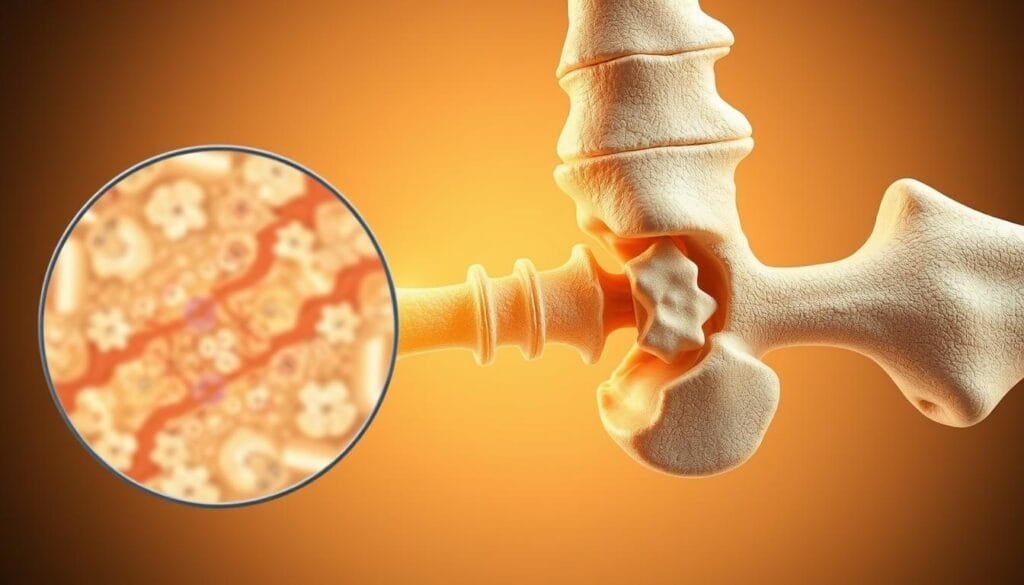

El Sistema Óseo y Muscular: Fuerza y Evolución

La evolución nos ha dotado de un sistema óseo que actúa como andamio biológico, mientras los músculos funcionan como motores de precisión. ¿Cómo logran trabajar en equipo para permitir desde movimientos delicados hasta proezas de fuerza?

El rol del cartílago y la osificación en el crecimiento

Al nacer, el 75% de nuestros huesos son cartílago flexible. Este material blando permite crecer hasta 20 cm por año durante la adolescencia. La osificación lo transforma gradualmente en tejido óseo sólido, un proceso que termina alrededor de los 25 años.

La mano humana muestra este diseño perfecto: sus 27 huesos trabajan con 34 músculos para realizar 58 movimientos distintos. «Sin el cartílago inicial, seríamos incapaces de desarrollar esta destreza», señala un estudio de biomecánica.

La importancia del glúteo mayor y el impacto en nuestra movilidad

El glúteo mayor no solo da forma a la silueta. Este músculo genera el 45% de la fuerza al caminar y estabiliza la pelvis. Su tamaño y potencia son clave evolutiva: permitieron a nuestros ancestros correr largas distancias.

- Mantener buena cantidad de masa muscular reduce 68% el riesgo de lesiones óseas

- Los huesos liberan osteocalcina durante el ejercicio, mejorando la función muscular

- La fuerza en glúteos aumenta 30% la eficiencia al subir escaleras

Esta simbiosis entre huesos y músculos demuestra que la naturaleza optimiza cada detalle para la supervivencia y el movimiento eficiente.